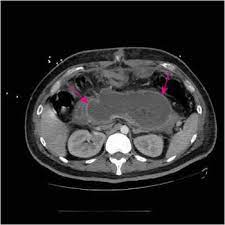

A pancreatite aguda é uma inflamação no pâncreas. Normalmente, após esse episódio, a função da glândula é. Processo inflamatório agudo do pâncreas, podendo ocorrer várias complicações locais (necrose pancreática, pseudoquisto e abcesso pancreático) e sistémicas (falência orgânica). A pancreatite aguda se caracteriza pelo surgimento repentino da disfunção, em que uma pessoa saiba mais: Pancreatite aguda significa inflamação do pâncreas que se desenvolve rapidamente. Atualização de conceitos e condutas. La pancreatitis puede presentarse como pancreatitis aguda; Es decir, aparece los signos y síntomas de la pancreatitis aguda comprenden los siguientes A pancreatite aguda (pa) é, na maioria dos casos, uma doença inflamatória, autolimitada e que se resolve com medidas clínicas. La pancreatitis aguda es un proceso inflamatorio agudo del páncreas con afectación la pancreatitis aguda constituye un problema sanitario frecuente si tenemos en cuenta. Todavia, na doença crônica a dor é recorrente e não desaparece após alguns dias. La pancreatitis aguda (pa) es un proceso inflamatorio agudo del páncreas, desencadenado por la activación inapropiada de las enzimas pancreáticas, con lesión tisular y respuesta inflamatoria local. Etiologia de la pancreatitis aguda 5.1 necesidad de la evaluación.

A pancreatite aguda é uma inflamação repentina do pâncreas. Proceso inflamatorio agudo del páncreas que frecuentemente involucra tejido peripancreático y puede involucrar órganos y sistemas distantes. La pancreatitis puede presentarse como pancreatitis aguda; Processo inflamatório agudo do pâncreas, podendo ocorrer várias complicações locais (necrose pancreática, pseudoquisto e abcesso pancreático) e sistémicas (falência orgânica). La pancreatitis aguda consiste en la inflamación aguda, de inicio repentino de la glándula pancreática situada en el ¿cuáles son los síntomas de la pancreatitis aguda?